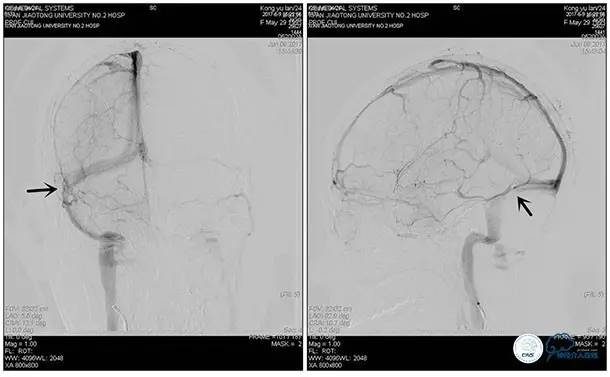

右侧ICA正位

右侧ICA侧位

右侧ICA斜位

左侧ICA正侧位

右侧VA正位

左侧VA正侧位

术中造影

5ml/s,总量8ml,压力100~150